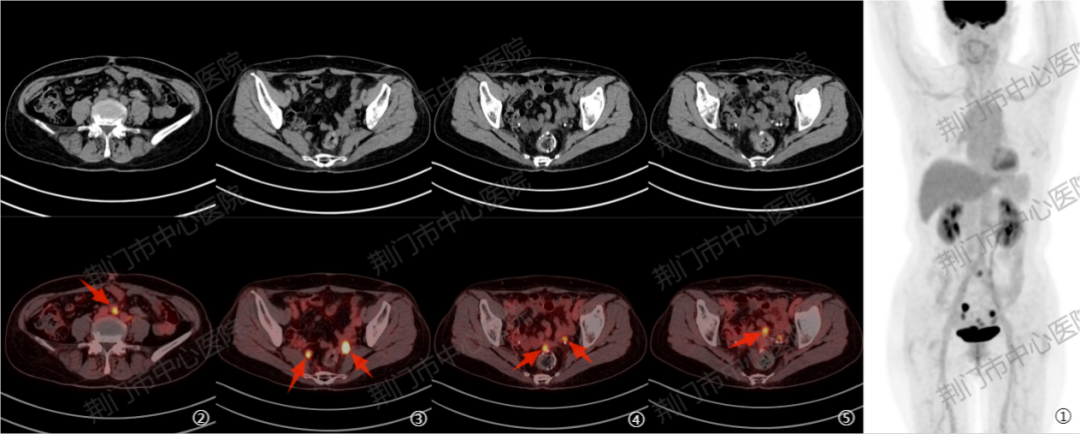

病例三:乙状结肠癌术后合并肝左叶转移瘤综合治疗后 1 周,发现 CEA 及 CA19-9 明显升高。PET/CT 显示肝左叶病灶代谢不高,考虑病灶活性受抑;盆腔多发淋巴结代谢增高,提示新发转移灶,为肿瘤标志物异常升高提供了影像学依据。